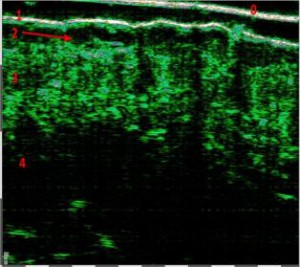

-Υπέρηχος Υψηλής Συχνότητας (HFUS) και Ιστολογία

Εφαρμογές δερματολογίας

-Κύριες εφαρμογές